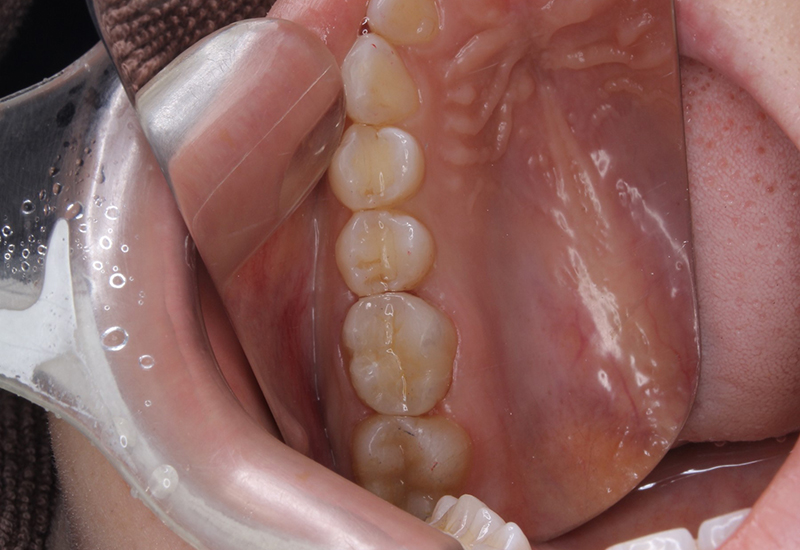

症例写真

治療前後の写真

綾瀬亀有ロハス歯科&矯正歯科のE-MAXインレー治療例治療前 綾瀬亀有ロハス歯科&矯正歯科のE-MAXインレー治療例治療後